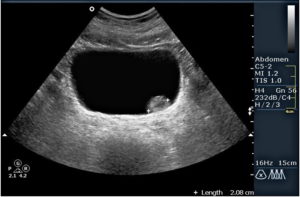

Нормы УЗИ

Ультразвуковое исследование имеет нормы, которые являются критерием для оценки состояния. Нормальный объем мочевого пузыря составляет до 550 мл у женщин, у мужчин до 750 мл.

Для оценки объема, исследование проводится при наполненном пузыре. Диагностическим критерием является остаточная моча.

У здоровых пациентов отсутствует, но допускается наличие в объеме до 50 мл. Если больше данного объема, свидетельствует об изменении формы мочевого, которое приводит к застою и становится причиной развития болезней.

Оценивается толщина стенки, в норме варьируется 2-4 мм. Истончение или утолщение стенки свидетельствует о патологии. Опасность представляет истончение, так как возрастает риск перфорации.

Стенка мочевого должна быть гладкой и иметь плавные закругленные формы. Значительное искажение, наличие тяжей и неестественные выпирания послужат признаком развитого спаечного процесса в малом тазу.